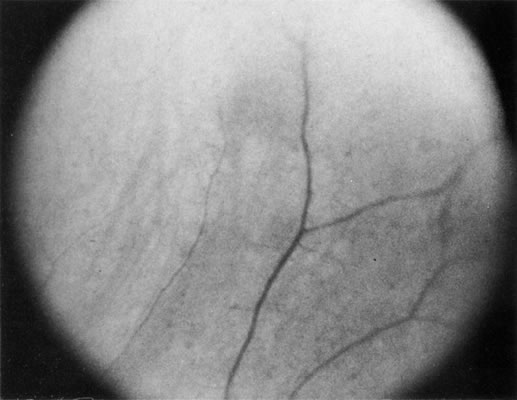

Necrotic melanomas account for approximately 5% of uveal melanomas; in the majority of cases, there is intraocular inflammation accompanying the cataract.7–9Figures 1 and 2 demonstrate a typical case. The patient had a long history of unilateral decreased vision. The eye had become painful 1 month before admission, and he was referred for evaluation of uveitis. Clinically, there was a dense, unilateral cataract with significant intraocular inflammation, which was manifested as a ciliary flush with 2+ cells and flare. Media opacity obscured all fundus detail. An immersion B-scan demonstrated a large intraocular tumor that was most consistent with a uveal melanoma. The eye was removed, and the diagnosis was confirmed histologically.10

|